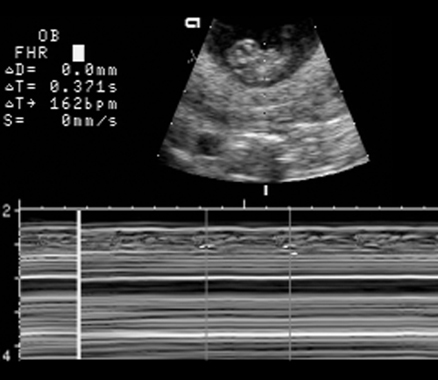

What is the normal fetal heart rate Answer

Fetal heart

Heart trace